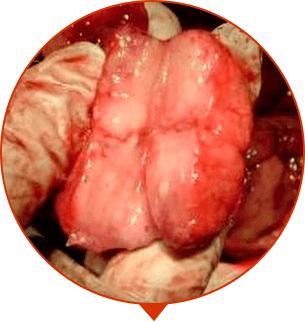

Chov va moyak xaltasida dag'al og'riqlar. Kattalashish, yallig'lanish. "Prostatit" tashxisi. Operatsiyaga tayyorgarlik. Moskvada ish safari paytida Pirogovkaga bordim. Tekshirishdi. Champion yozib berishdi. Bir oydan keyin hammasi bartaraf bo'ldi. Parvozlar odatdagidek, og'riq, achishishlar yo'q

****, Termiz